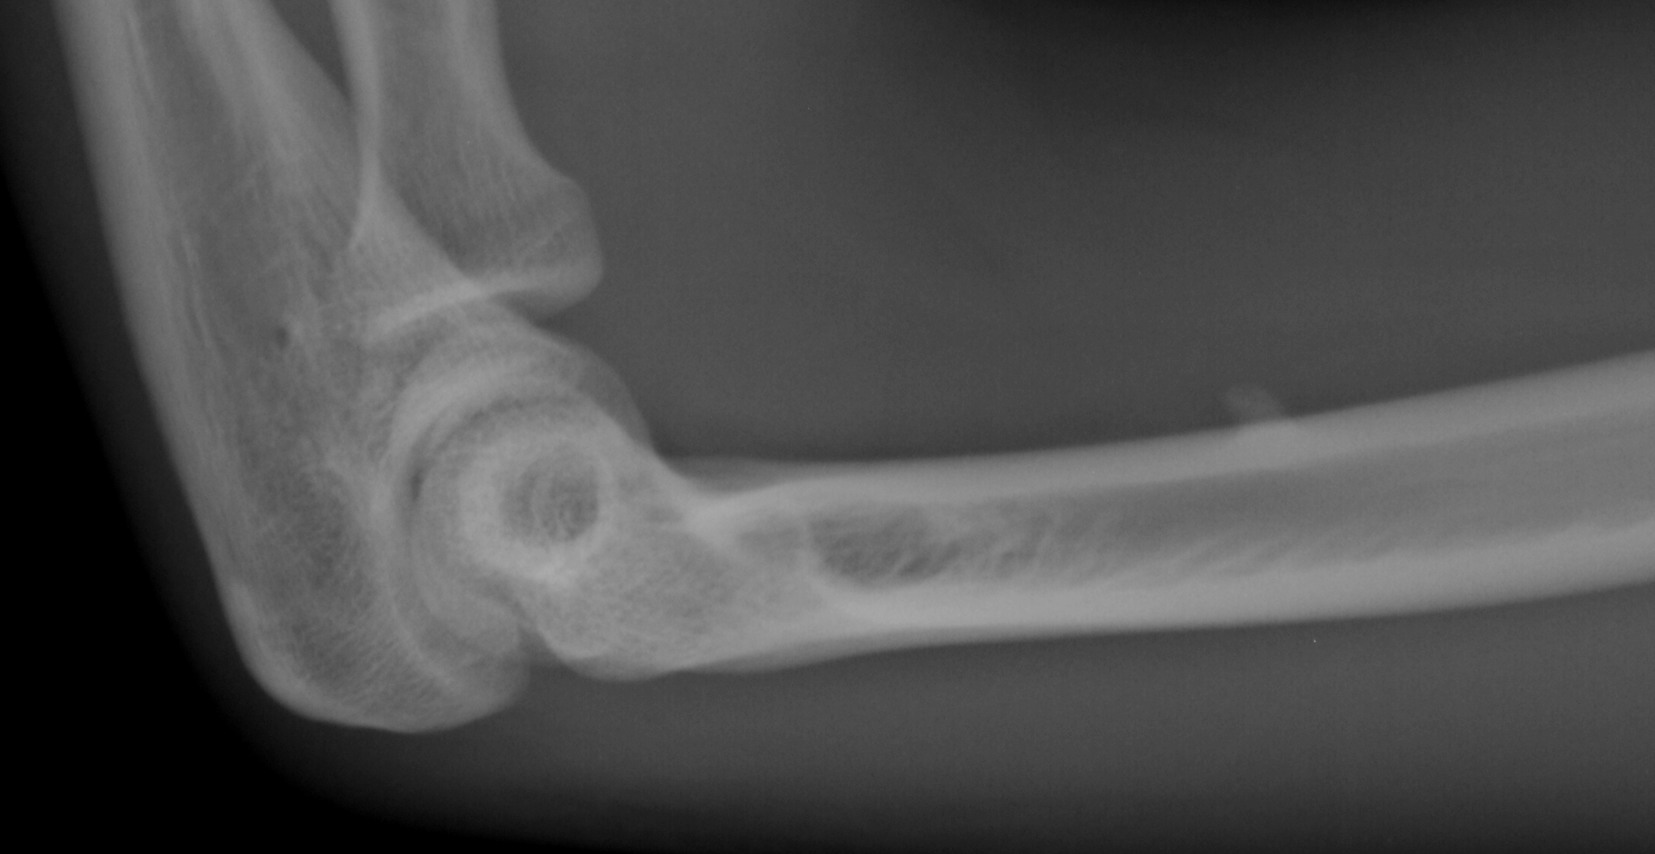

骨肿瘤x线图片,骨肉瘤x线图片

x11628:肱骨下端内侧良性骨肿瘤,求会诊 - x线病例 医

骨肉瘤x线图片

骨肿瘤x线

骨巨细胞瘤x线图片

骨肉瘤x线